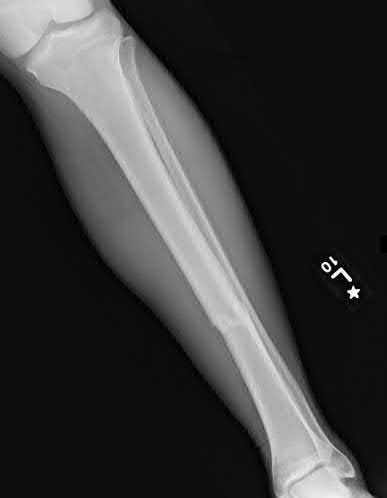

What is the most common type of malalignment after intramedullary nailing of distal 1/3 extra-articular tibia fractures using a infrapatellar approach when compared with plating?

The most common type of malalignment after intramedullary nailing of distal 1/3 extra-articular tibia fractures using an infrapatellar approach when compared with plating is valgus malalignment.

Fixation of distal one-third tibial shaft fractures can be successfully treated with either intramedullary nailing or plating. The literature describes advantages and disadvantages to both approaches, however intramedullary nailing has been shown to lead to increased rates of valgus malunion. Recent studies have shown that using a suprapatellar approach may decrease the incidence of valgus malalignement.

Vallier et al performed a randomized prospective study to compare plate and nail stabilization for distal tibia shaft fractures by assessing complications and secondary procedures. One-hundred and four patients were randomized to either reamed intramedullary nailing, or medial distal tibia plate fixation.

Primary angular malalignment was identified in 17 patients (16.3%). This included four patients treated with tibial plating (8.3%) and 13 patients treated with nails (23%, P = 0.02). Eight of these (7.7% of all patients) had malalignment between 6° and 10° of angulation. Valgus was the most common

angular deformity, accounting for 70% of angular deformity cases.

Avilucea et al. looked at the immediate postoperative alignment of distal tibia fractures (within 5 cm of the tibial plafond) treated with suprapatellar intramedullary nail (IMN) insertion compared with the infrapatellar technique. They found primary angular malalignment of ≥5 degrees occurred in 35 (26.1%) patients with infrapatellar IMN insertion and in 5 (3.8%) patients who underwent suprapatellar IMN insertion. They conclude suprapatellar IMN technique results in a significantly lower rate of malalignment compared with the infrapatellar IMN technique.